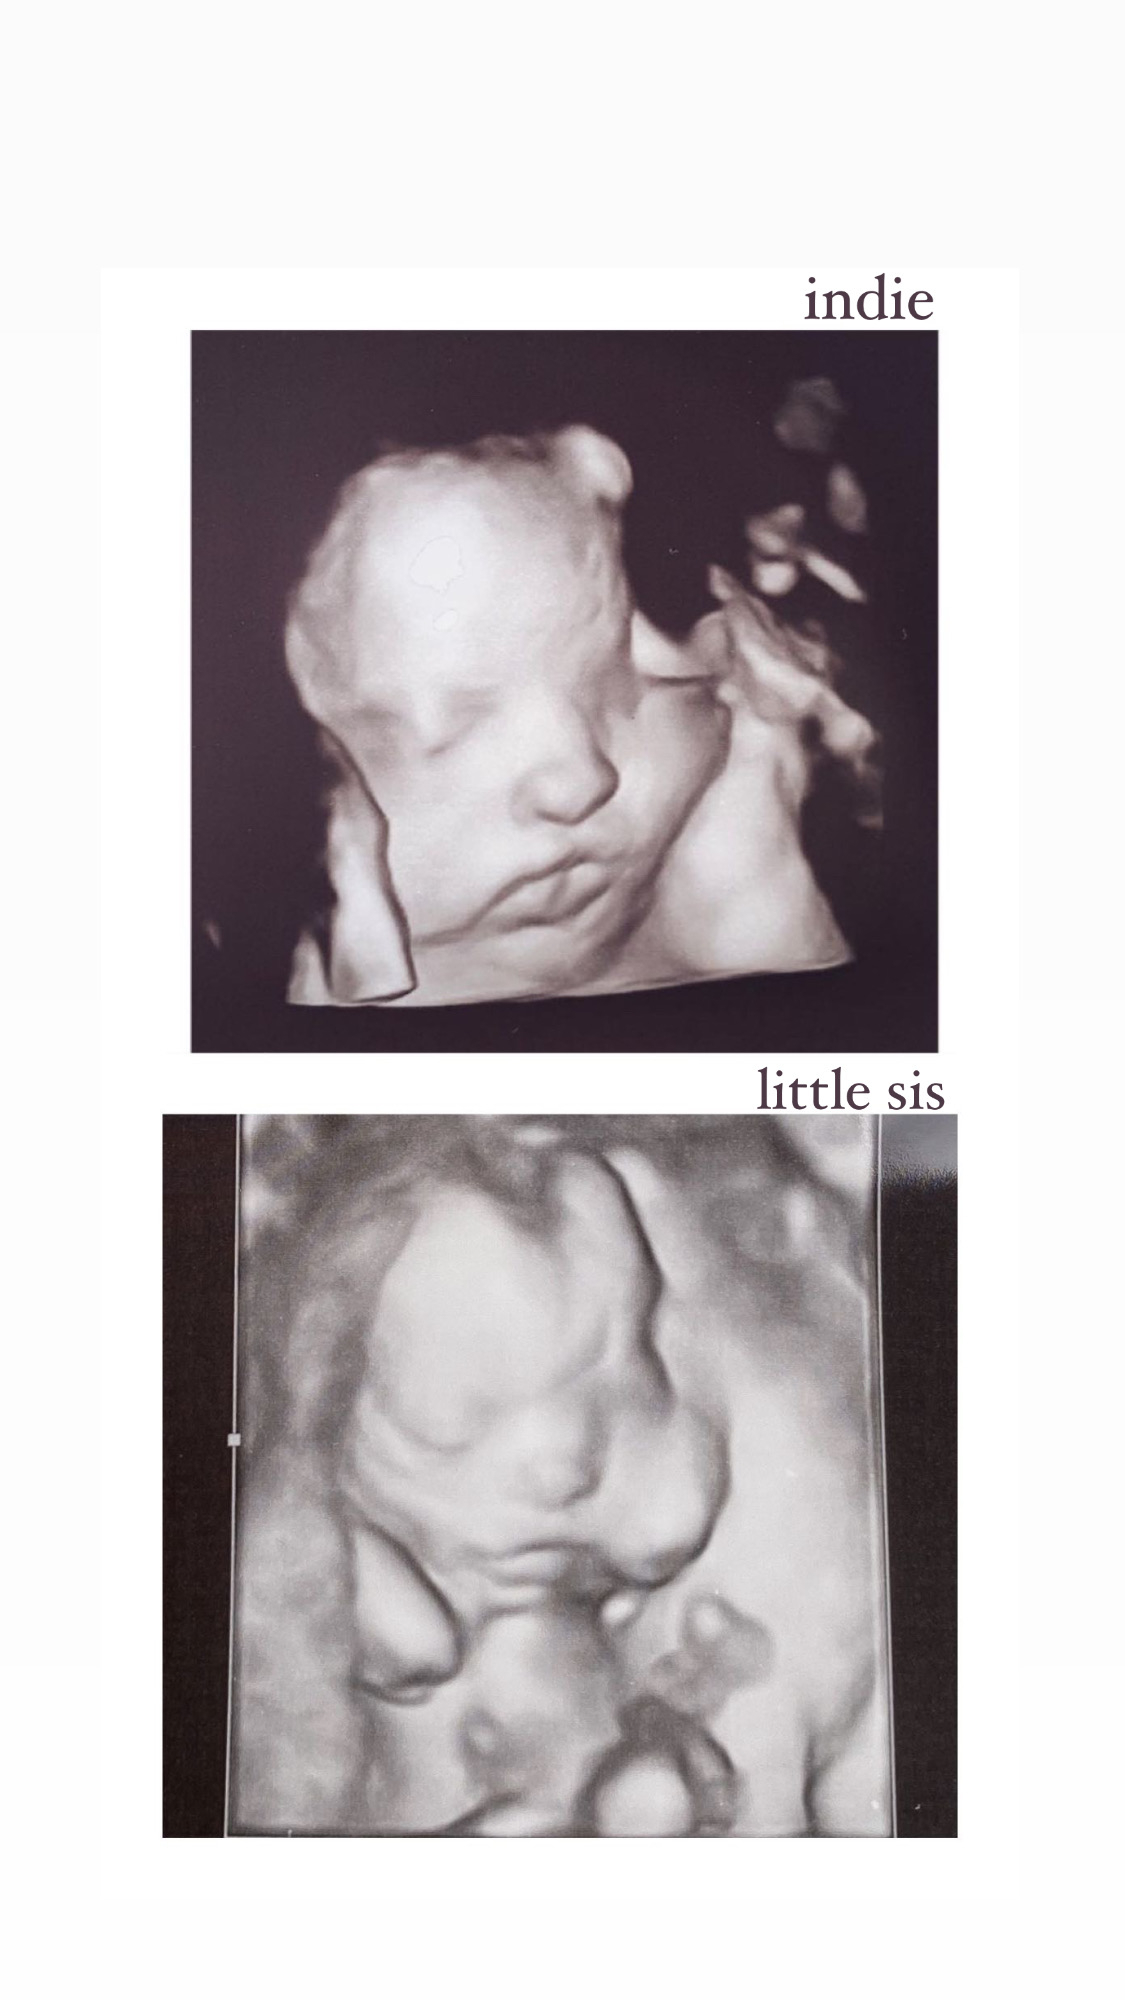

AS today and baby looked great and healthy! We stayed Team Green for the 4th time. The tech said she could definitely tell if it was a boy or girl, but I stayed firm and told her we for sure didn’t want to know! This was the very first time I’ve had a 3D ultrasound- Baby has similar features to his/her big sisters! Can’t wait to hold this cutie in 20 weeks 🥰